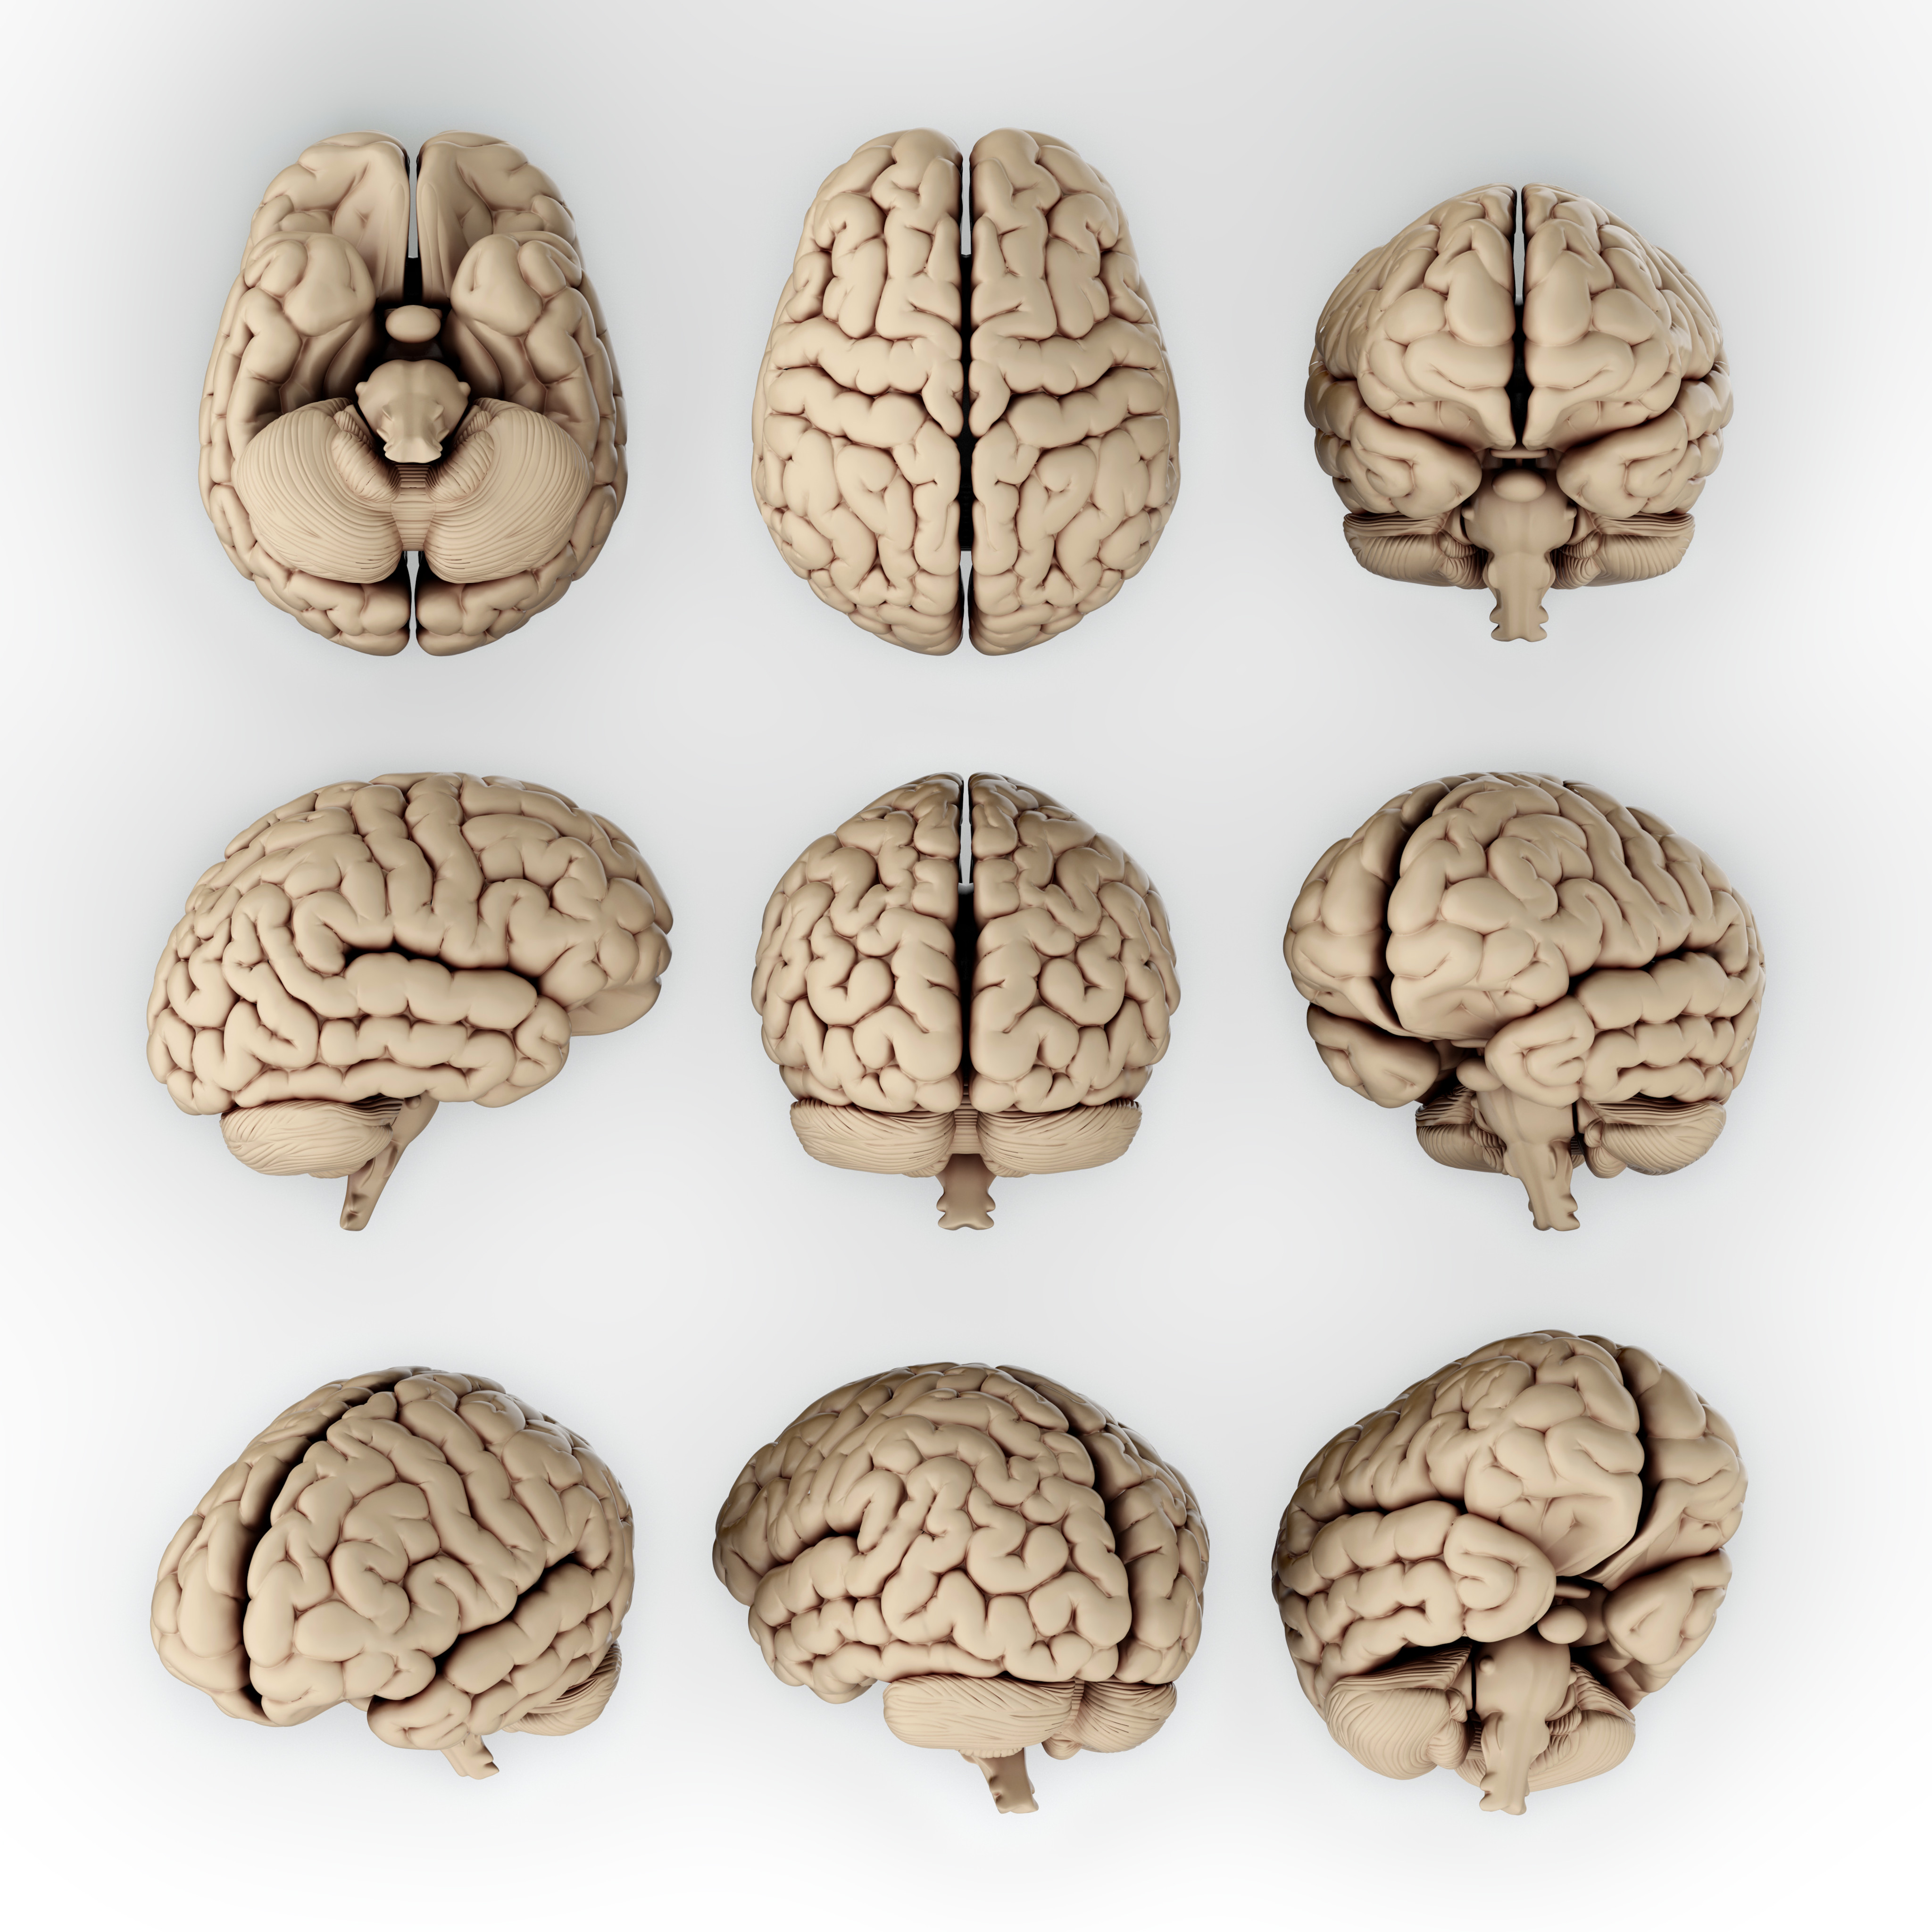

대뇌(Cerebrum)

뇌의 대부분을 차지하며 좌우 2개의 반구로 구성되어 있습니다. 감각, 지각, 운동, 기술, 상상력, 추리력, 언어능력, 통찰력 뿐만 아니라 자율신경계 조절, 호르몬 조절, 항상성 유지 등의 기능을 수행합니다.

좌우 2개의 반구로 되어있으며 반구는 뇌들보에 의해 서로 연결됩니다. 대뇌에서 돌출된 부분을 이랑이라고 하고 주름져 안으로 들어간 부분을 고랑이라고 하는데, 이들의 모양에 따라 전두엽(이마엽), 관자엽(측두엽), 마루엽(두정엽), 뒤통수엽(후두엽)으로 나눌 수 있습니다.